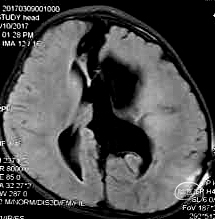

7岁 小学一年级,成绩较差、余无神经功能障碍

脑组织形态发育接近正常